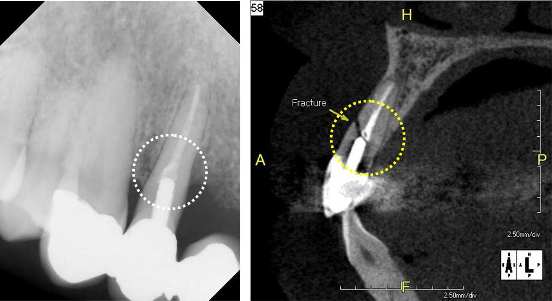

Case1: Root Fracture

The regular 2D x-ray image suggests a possible issue with an endodontic treatment. However, it is not sufficient for a clear diagnosis. The sagittal image of the 3D CBCT scan reveals a root facture.

2D (Dental image) 3DMPR (Sagittal)